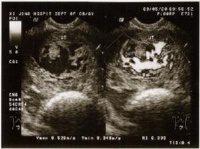

六、无胎儿可及 闭经8周前后,B超监测,未发现有胎囊、胎心及胎儿。孕周、甚至18周仍不感有胎动,听不到胎心。B超扫描显示雪片样影象而无胎儿影象。

B超腹部扫描可见子宫内可能有大小不等的暗区,系宫腔内积血所致。还能发现胎,即除有雪花光片外,还可能有胎儿及/或胎盘影像。B超仪诊断无任何创伤,确诊率高,实为确诊葡萄胎的有力措施。

B超腹部扫描可见子宫内可能有大小不等的暗区,系宫腔内积血所致。还能发现胎,即除有雪花光片外,还可能有胎儿及/或胎盘影象。B超仪诊断无任何创伤,确诊率高,实为确诊葡萄胎的有力措施。